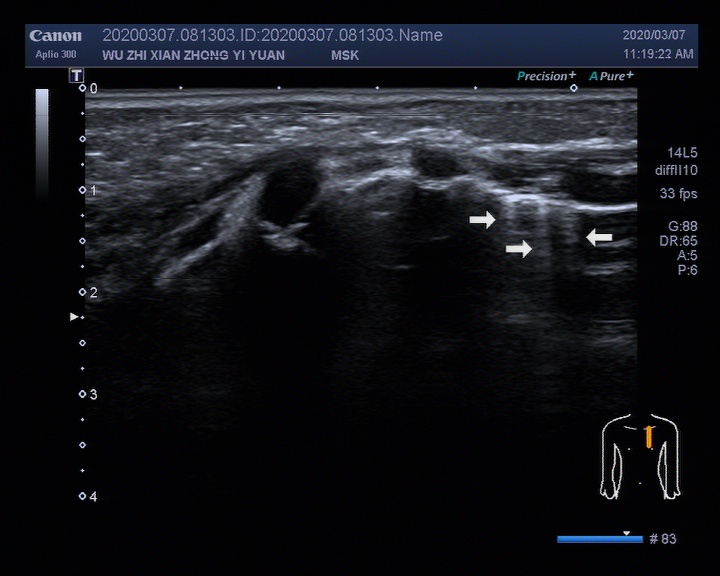

▎5个月婴儿肺脏超声检查超声图像

image011

上图箭头所示:左侧胸骨旁线3-4肋间可见三条B线,呈“火箭征”,间隔大于3mm。